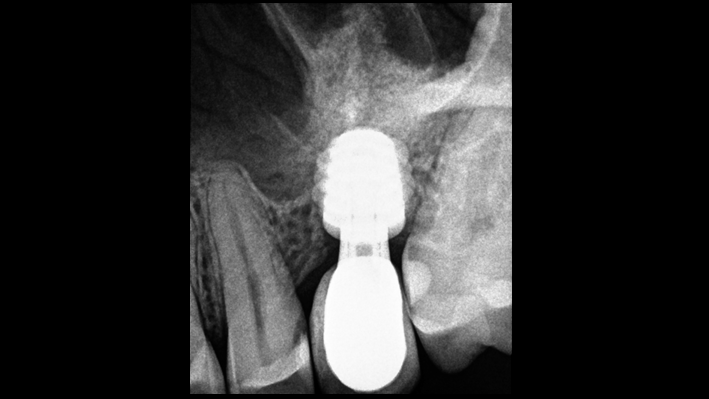

Clinical case: Ridge splitting technique using SmarThor + AnyRidge as expander

- Courtesy of Dr.Kwang-Bum Park, Korea -

AnyRidge, ridge splitting, GBR, Dr. Kwang-Bum Park, mandibular posterior, SmartThor, Mega-Oss, thin ridge, bone regeneration

Products:

AnyRidge implant system. SmarThor, Mega-Oss